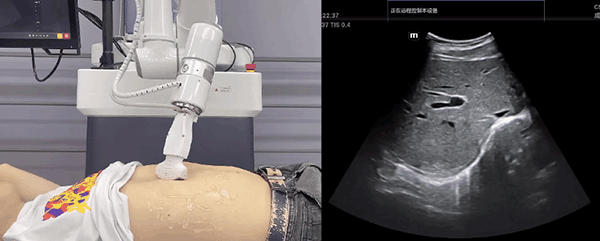

艾利特機(jī)器人末端搭載超聲探頭,可以對(duì)淺表小器官和外周血管、腹部(肝、膽、胰、腎等器官)進(jìn)行超聲檢查。

普羅超聲聚焦治療機(jī)器人

目前,艾利特機(jī)器人在生物醫(yī)藥、醫(yī)療健康領(lǐng)域的賦能已有顯著進(jìn)展,艾利特協(xié)作機(jī)器人應(yīng)用場(chǎng)景覆蓋了臨床試驗(yàn)、試管檢測(cè)、拭子采集、試管搬運(yùn)、熒光檢測(cè)、康復(fù)治療、超聲掃查、導(dǎo)診、消毒、微創(chuàng)治療、針灸刮痧等。